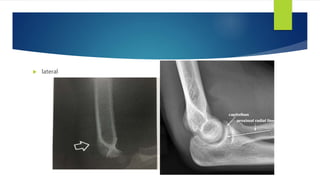

 AP view

Baumann angle

 lateral